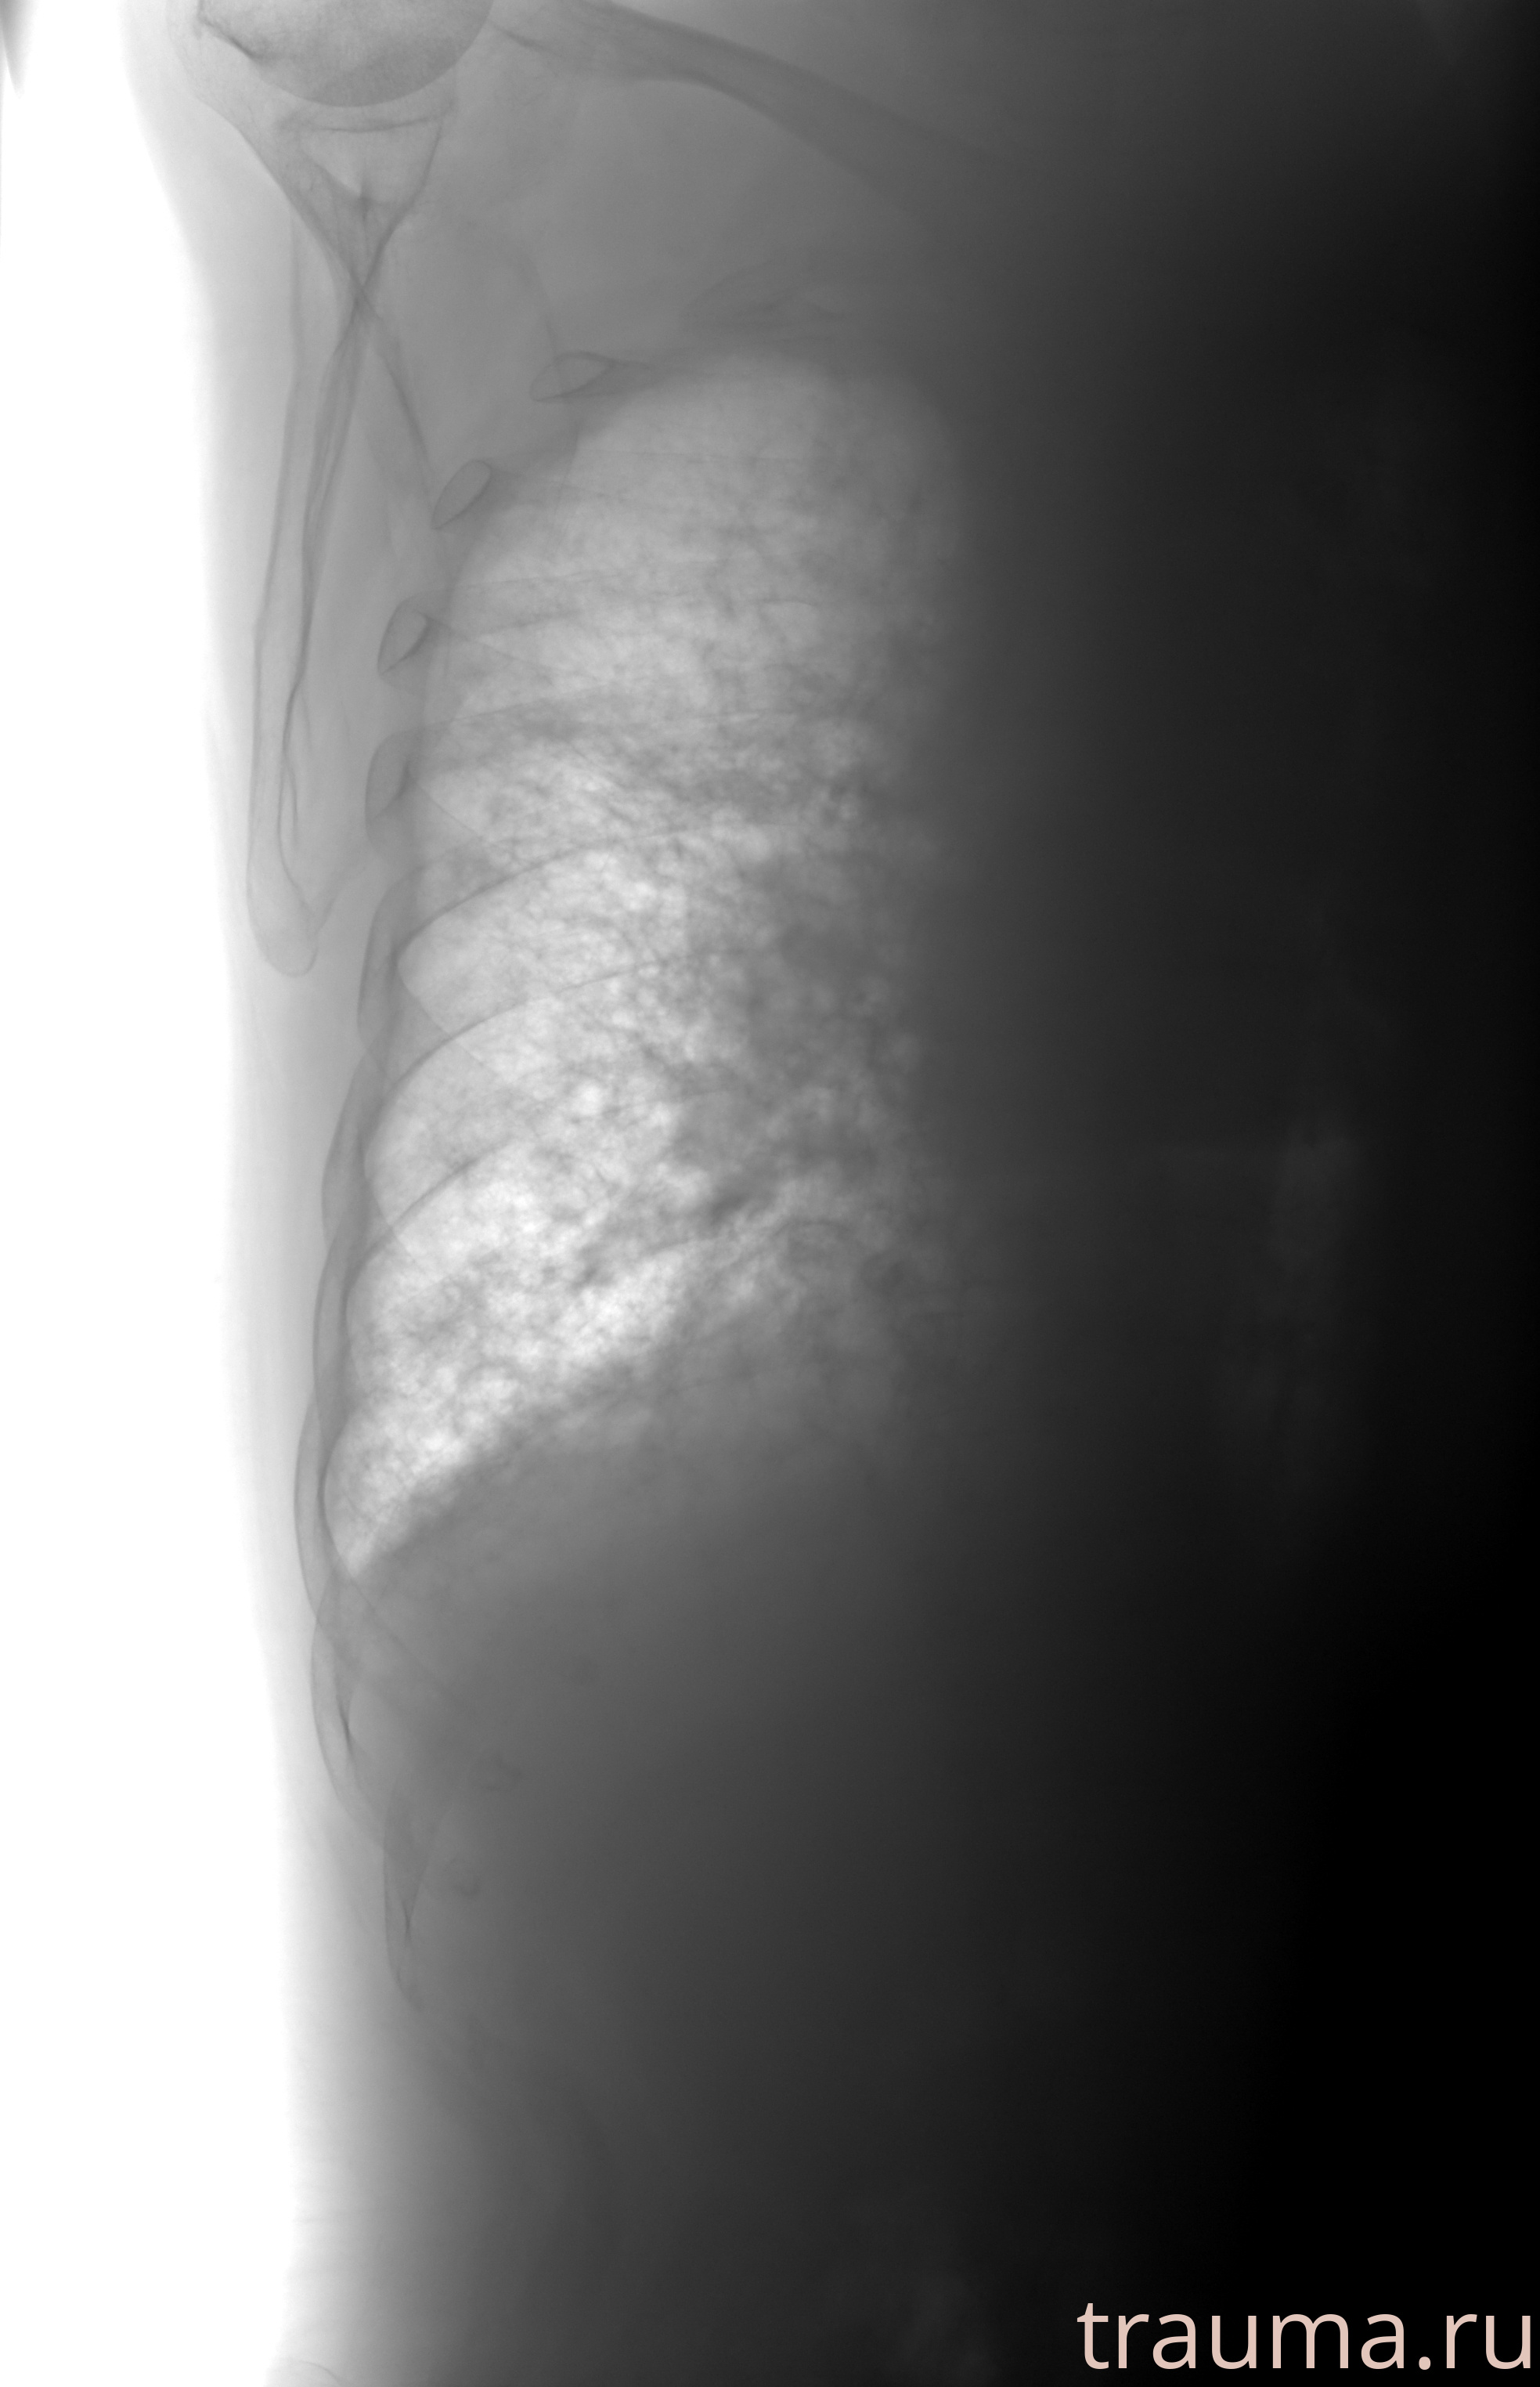

Рентгенограммы

Рентген на дому: по вашему адресу приезжает врач-рентгенолог, травматолог-ортопед с мобильным рентгеновским аппаратом, проводит диагностику травмы или заболевания, делает необходимые рентгенограммы, дает рекомендации по дальнейшему лечению. Получить качественные снимки в домашних условиях возможно благодаря уникальной методике, разработанной МосРентген Центром для института  Склифосовского

при переломе шейки бедра и пневмонии от компании МосРентген Центр - партнера Института имени Склифосовского